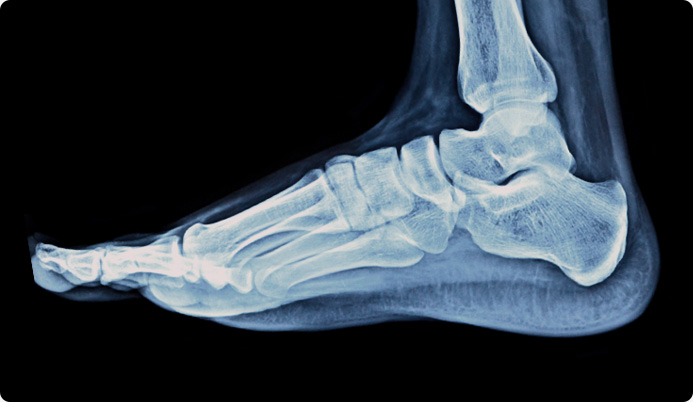

거골의 내측부 연골 병변에 대해서 관절경을 통해 미세천공술과 콜라겐 주입술을 시행하였으며,

수술 5개월째 결손 부위에 연골이 잘 생성되어 있는 소견이 관찰되었습니다.